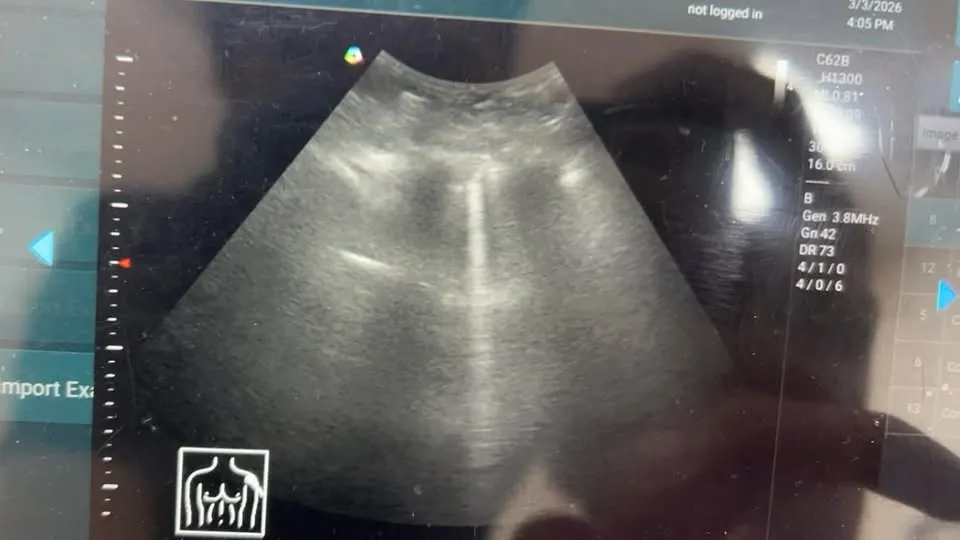

「臨床炸彈。所有醫師必須要小心的表現」

有一名婦女來掛號,在診間裡就聽到候診區傳來很嚴重且充滿痰音的咳嗽聲。

立馬叫號,走進來力氣尚可,但呼吸表現有點淺快。